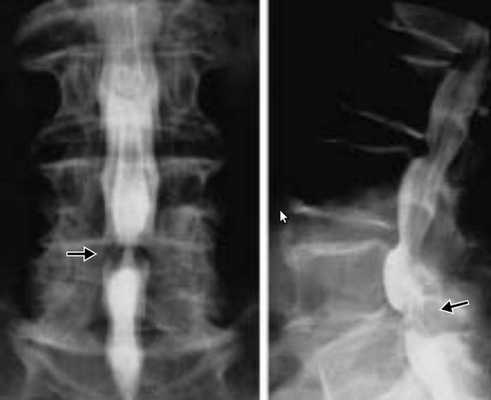

КТ пояснично-крестцового отдела позвоночника показала состояние после перенесённого спондилодисцита L2-L3 (воспалительного заболевания инфекционного характера) с разрушением тела L3 позвонка и кифотической деформацией (искривлением позвоночника) на данном уровне.

Состояние после перенесённого спондилодисцита L2, L3 позвонков с формированием абсолютного стеноза (критического сужения просвета в позвоночном столбе) на уровне L2-L3 и развитием нижнего парапареза